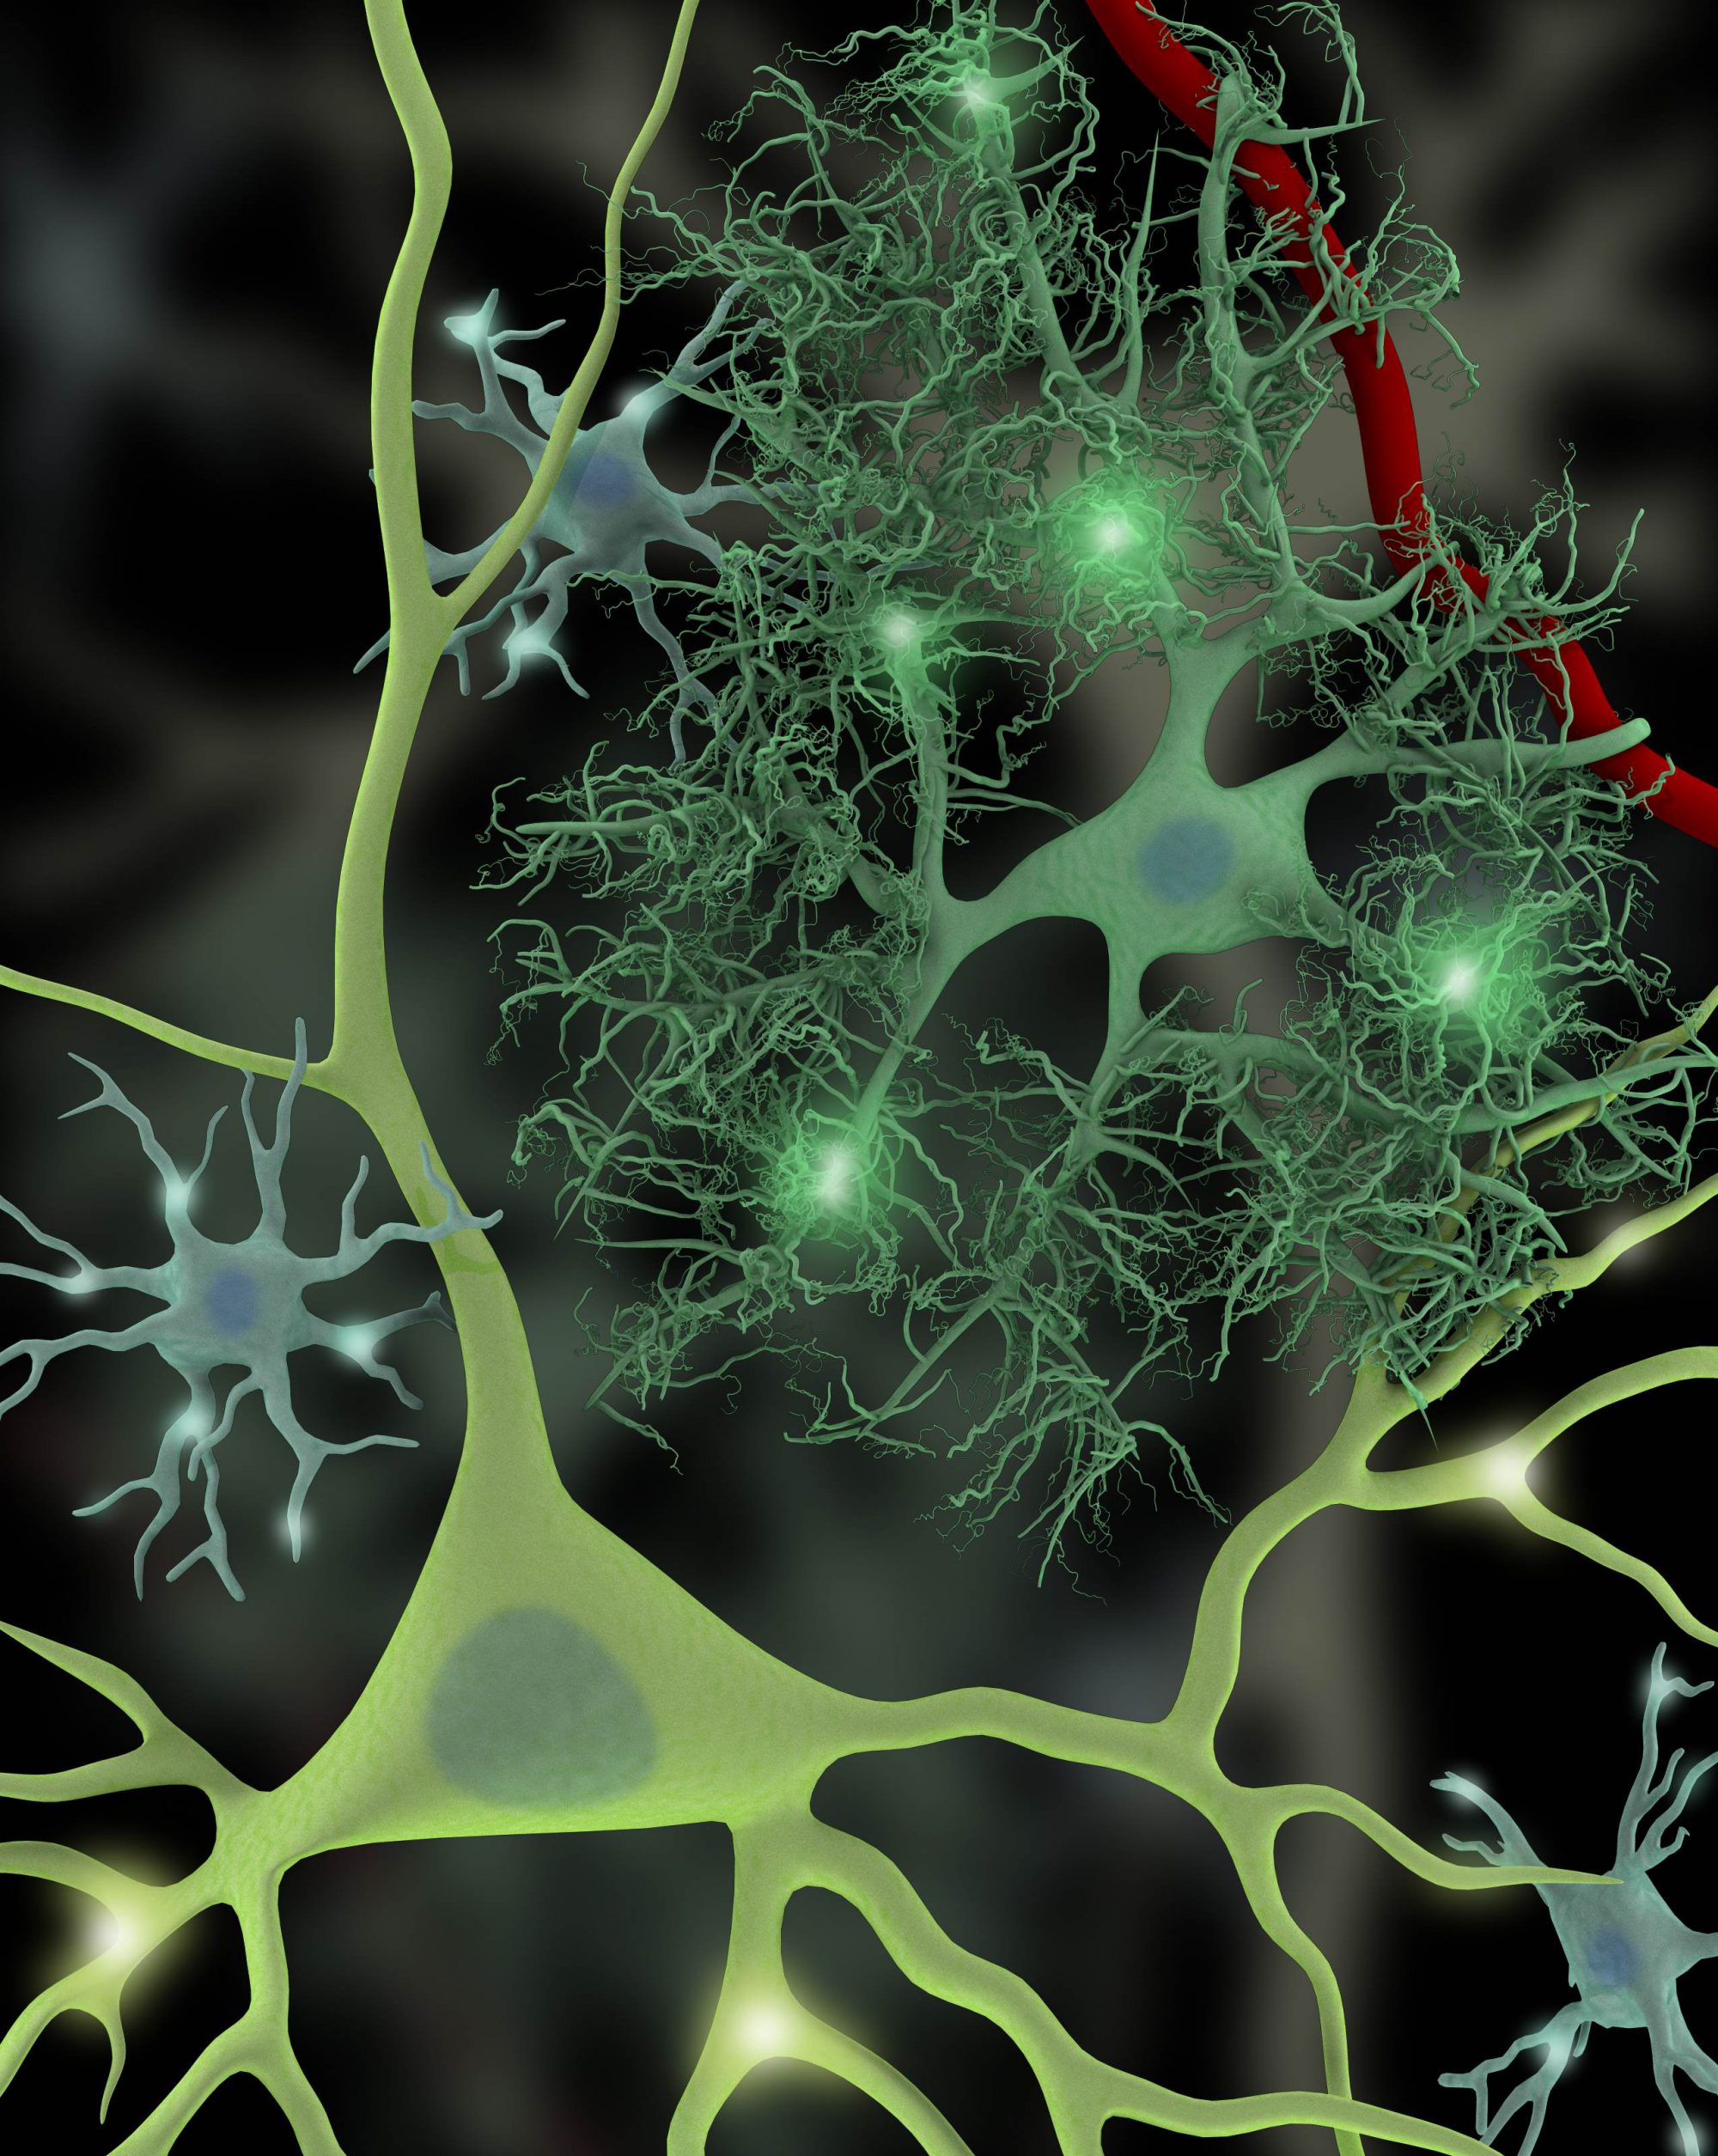

You can help support our work directly. Your donations can help fund cutting-edge research to better understand how disruptions of neuronal-glial crosstalk will contribute to disease processes such as ADHD, epilepsy, and insulin resistance with the hope of revealing pathways suitable for manipulation to alter disease progression in the central nervous system.